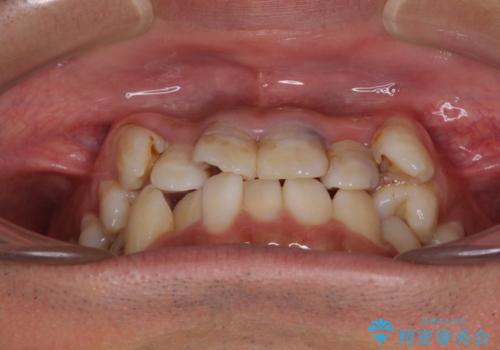

デコボコと変色した前歯 抜歯矯正と審美歯科治療

- 八重歯と上顎前歯の変色を気にして来院された患者様です。

上下ともに八重歯が顕著であったため、上下左右の第一小臼歯4本を抜歯し、ワイヤー装置での抜歯矯正を行うこととしました。

前歯は根管治療が必要な歯を事前に根管治療を行い、矯正治療後にオールセラミッククラウンにて補綴治療を行うこととしました。